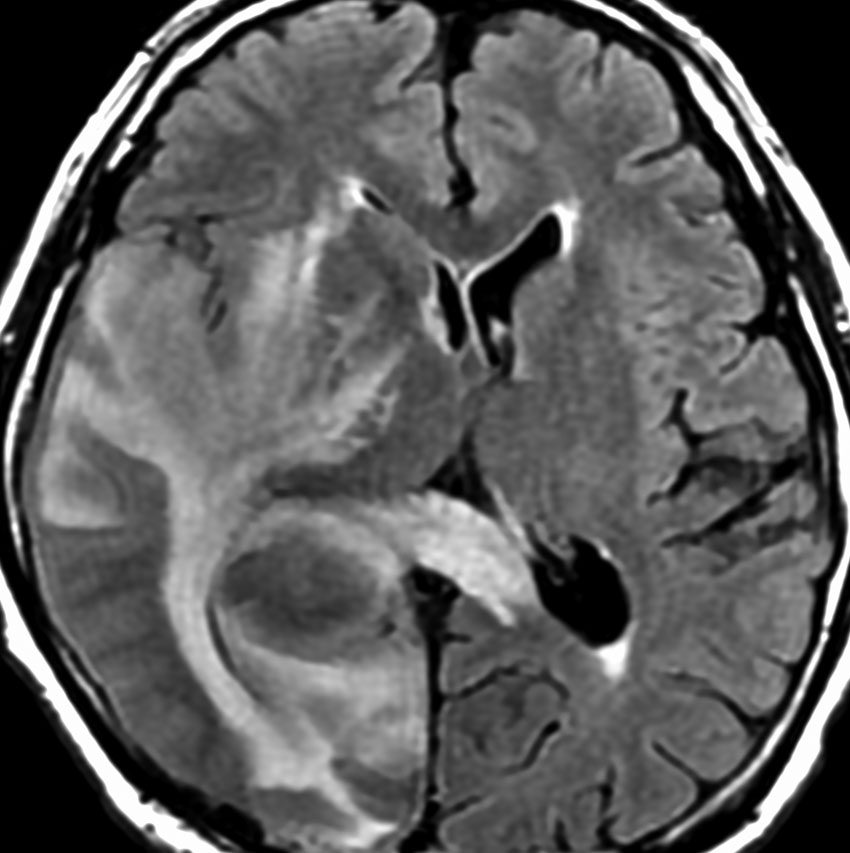

左から,1回目の再発,2回目の再発,3回目の再発です。再発するたびになんとか治療はできるのですが,違った場所に再発してきてだんだん治療が効かなくなってくることが多いです。このような現象から,脳のリンパ腫は脳に発生するのではなくて,体のどこかに原発巣があるのではないかという考えもあります。もちろん、こんな再発をしないで治ってしまう患者さんも多いです。